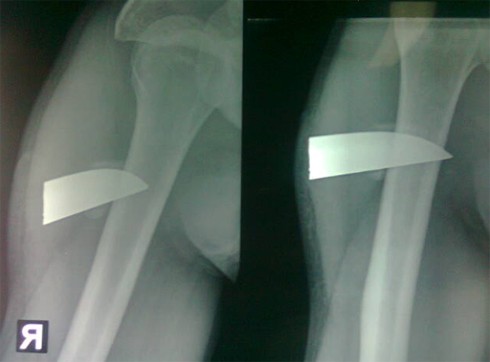

Ngày 28.10 các bác sĩ Bệnh viện Hữu nghị Việt Nam - Cu Ba Đồng Hới đã phẫu thuật và rút ra lưỡi dao dài gần 7 cm trong cánh tay của bệnh nhân Trần Bắc Nam, 22 tuổi ở xã Xuân Trạch, huyện Bố Trạch.

Ảnh chụp X-quang mũi dao nằm xuyên vào tay bệnh nhân.

Chụp X-quang, các bác sĩ phát hiện dị vật trong vết thương, phẫu thuật lấy ra lưỡi dao còn mới.

Theo các bác sĩ, may mắn là lưỡi dao cắm sâu vào tận xương nên không di chuyển, không ảnh hưởng đến các tổ chức xung quanh. Nếu không, bệnh nhân có thể liệt cánh tay vì lưỡi dao cắt đứt dây thần kinh, cơ, mạch máu bên cạnh.